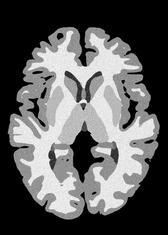

4.2 Registration to a 100 micron ex-vivo brain MRI volume

To showcase the efficacy of our method on real large scale images, we register a 250 in-vivo MRI image (Lüsebrink et al., 2017) to a 100 ex-vivo FLASH human brain volume (Edlow et al., 2019). This represents an inverse problem with more than 11.2B optimizable parameters (compared to 20M for clinical datasets), or 44.8GB of GPU memory. The entire problem does not fit on most GPUs, necessitating distributed multimodal registration. We optimize a composite transform - affine followed by a diffeomorphic mapping; details can be found in Section E.1. Multimodal deformable registration took 58 seconds on 8 NVIDIA A6000 GPUs, which is unprecedented at this resolution. Fig. 6 shows qualitative results, highlighting the ability to register highly detailed structures such as cerebellar white matter; these structures are not visible at macroscopic scales. The resultant advantages of performing registration at this scale can allow researchers to characterize the neuroanatomy at microscopic resolutions and allow morphometric analysis of cortical layers and subcortical nuclei among other structures.